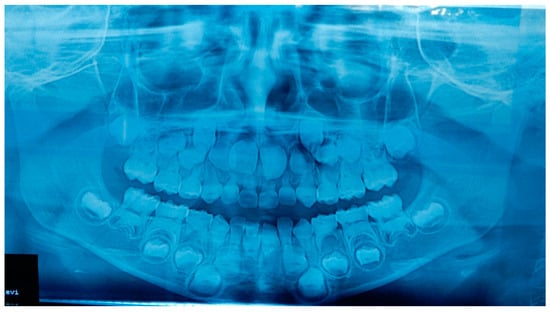

2.1. Patient A

2.2. Patient B

2.3. Father